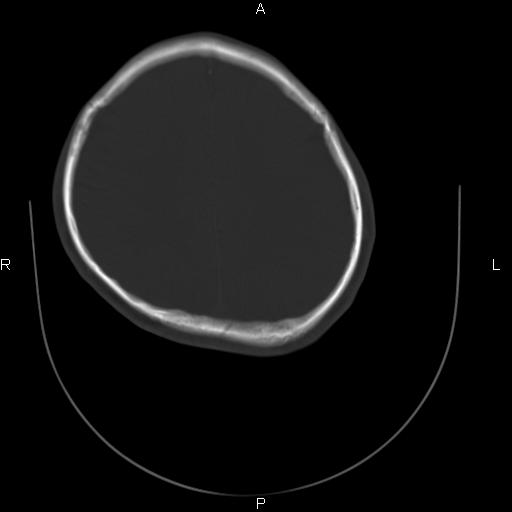

标题: CT27115:大家看一看,这孩子的颅骨表现? [打印本页]

标题: CT27115:大家看一看,这孩子的颅骨表现?

两名中学生打架,脑质内未见异常,未上传。

两例——颅骨结构正常,未见明显骨折征象。